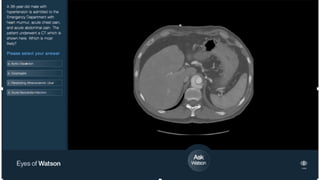

The

Medical

Sieve §Build  a  fast  anomaly  detection

engine

– Quickly  filters irrelevant  images

– Highlights  disease-­depicting  regions

– Flags  coincidental  diagnosis

§ Intended  as  a  radiology  assistant

– Clinicians  still  do  the  diagnosis

– Machine  reduces  workload

– Machine  performs  triage/decision

support

Given  history  of  the  patient  and  images  of

a  study

Is  there  an  anomalous  image  here?

If  so,  where  is  the  anomaly  ?

Describe  the  anomaly